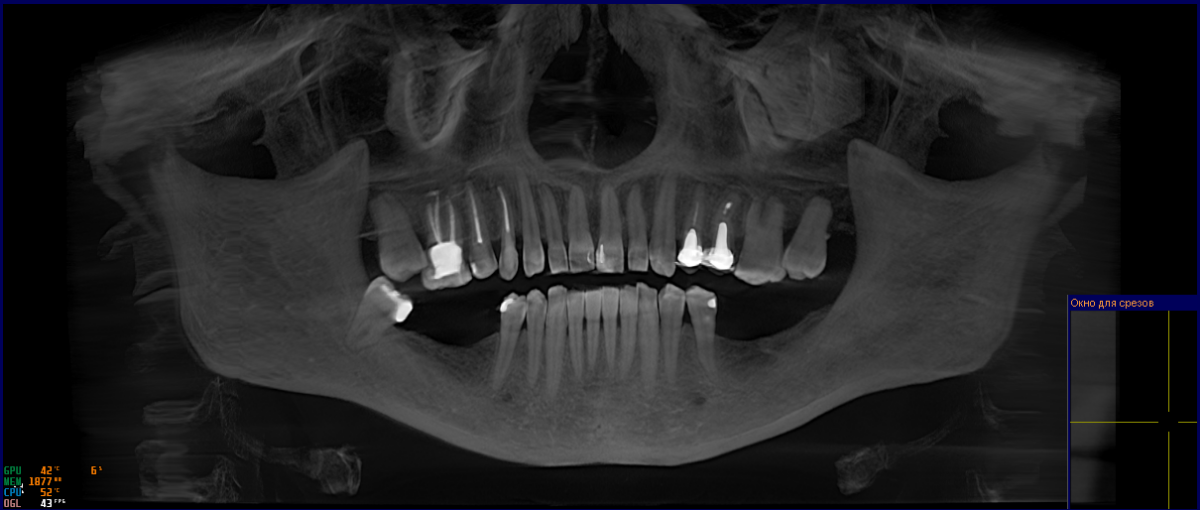

angryberry Опубликовано 4 марта, 2025 Поделиться Опубликовано 4 марта, 2025 (изменено) Здравствуйте! Прошу консультацию для моей мамы (маме 52 года). Планируется имплантация 36, 37, 46, 47. 37 удален в апреле 2024 г., 36, 46, 47 – более 20 лет назад. Мама сходила на консультацию к трем хирургам, их мнения следующие: Хирург №1: не смотрел полость рта и КТ, смотрел распечатку ортопантомограммы. Сказал, что поставит 36, 37 сначала, через полгода – 46, 47. Сказал, что не надо делать пластику десны, возможно, понадобится наращивание костной ткани со стороны 46, 47, а для 36, 37 костной ткани хватает. Хирург №2: не смотрел полость рта, но посмотрел КТ. Сказал, что поставит импланты Премиум, так как они короткие, у них широкая поверхность. Именно такие потому, что не хватает костной ткани с обеих сторон, а также близко расположен нерв. Сказал, что поставит 36, 37 сначала, потом – 46, 47. Не надо делать пластику десны. Хирург №3: посмотрел и полость рта, и КТ. Сказал, что поставит сначала 36, 37, и нужна будет пластика десны, а потом поставит 46, 47, возможно, пластика десны не нужна будет. Доктор сомневается, что сможет поставить коронку на 37, так как мало места, назначена консультация стоматолога-ортопеда. Вопросы следующие: Действительно ли есть возможность повреждения нерва из-за близкого расположения? Необходимо ли наращивание костной ткани? Где? Необходима ли пластика десны? Где? Какой из предложенных планов наиболее корректный с учетом объективных данных? После имплантации одной стороны как долго можно повременить с имплантацией другой стороны? (Вопрос исключительно финансовый) Есть ли еще какие-то нюансы, которые ни один из врачей не озвучил, но о которых маме, как пациенту, нужно знать? Я пыталась сделать скрины КТ, но, к сожалению, ни на одном компьютере не получилось открыть диск, так что прилагаю ссылку на заархивированное содержимое диска. Пожалуйста, не пройдите мимо! Мы живем в Витебске, в теме про докторов не нашла ничего про свой город, так что надежда на вас, уважаемые доктора. Если нужны дополнительные данные, я предоставлю. https://transfiles.ru/m449w Изменено 4 марта, 2025 пользователем angryberry Ссылка на комментарий

Женька Опубликовано 5 марта, 2025 Поделиться Опубликовано 5 марта, 2025 (изменено) Я за удаление 4.8, имплантацию 4.7-4.6, 3.6-3.7 Зубы 7 на верхней челюсти есть, значит и антагонисты им нужны. Шаблон можно сделать, лишним не будет, облегчит работу врача. Но при должном опыте и без шаблона можно поставить. Без снимков или осмотра в полости рта - это просто мнение из интернета. Плюс интрузию в 1 сегменте запланировать. Ортопед должен об этом был сказать. Изменено 5 марта, 2025 пользователем Женька 1 Ссылка на комментарий

Женька Опубликовано 6 марта, 2025 Поделиться Опубликовано 6 марта, 2025 @angryberryуф, упустил из виду. В любом случае, я за восстановление в полной мере. Не будет 7, верхние 7 поползут вниз (что уже случилось в области верхних правых зубов (во рту, не на снимке). Доползут до окклюзионного блока - придётся удалять. 1 Ссылка на комментарий

Женька Опубликовано 7 марта, 2025 Поделиться Опубликовано 7 марта, 2025 18 минут назад, angryberry сказал: Как вы на это смотрите? Нормально. Но зависит от степени необходимого "спиливания" зуба. Если спиливать нужно много, то я бы шёл по пути ортоимплантов и интрузии, как писал выше коллега. НО! с другой стороны, зубы справа уже депульпированы, требуют покрытия коронками, значит можно и подшлифовать. Слева действительно живые, по снимку. Поэтому лучше их не трогать, на мой взгляд лишний раз. Замок прижимания... доктор как раз видимо имел ввиду окклюзионный блок. Снизу, по моему мнению, без десневых пластик особо не обойтись. Ссылка на комментарий